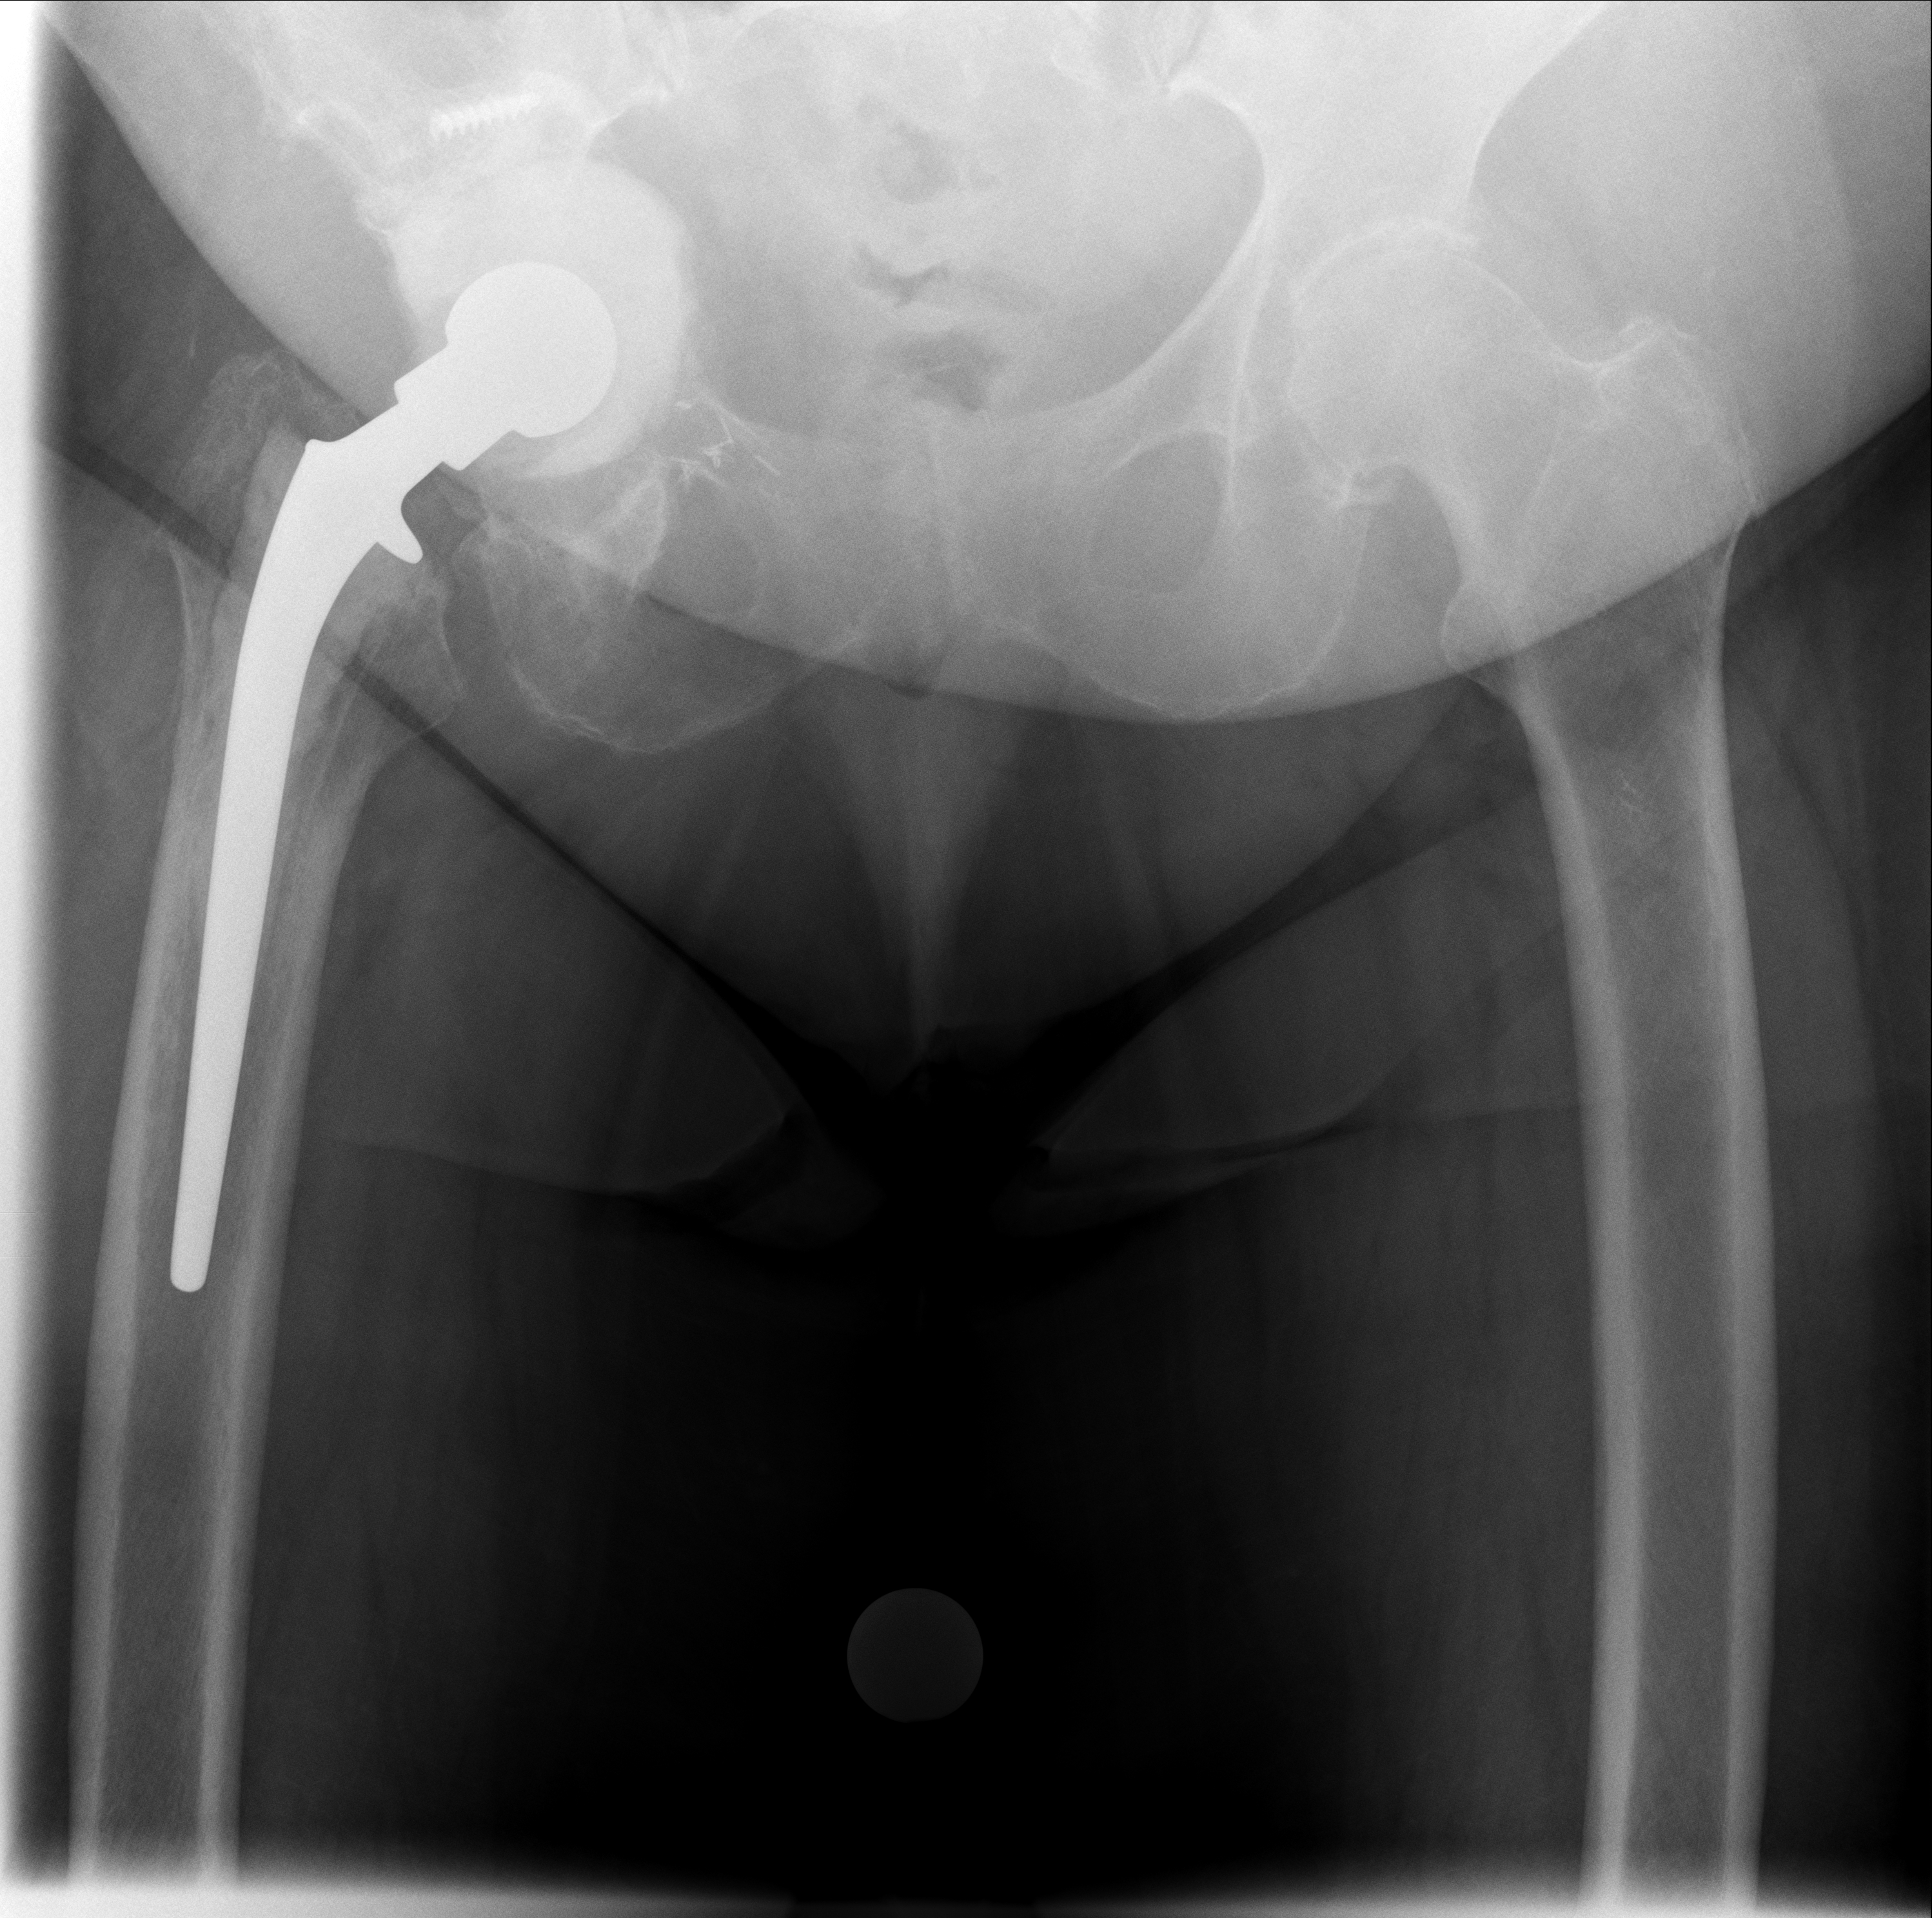

Röntgenbilder im Verlauf: korrekte Lage → Luxation → neue TEP nach Wiedereinbau

07.10.2024 - Korrekt

Röntgen Oktober 2024

Prothesenkopf sitzt korrekt in der Pfanne

21.11.2025 - Luxiert

Röntgen November 2025

Prothesenkopf aus Pfanne luxiert

24.02.2026 - Neue TEP

Röntgen Februar 2026

Neue Hüft-TEP rechts nach Wiedereinbau

Akuter Befund: Hüftprothesen-Luxation

Vergleich der Röntgenbilder zeigt eine Luxation der Hüft-TEP rechts. Der Prothesenkopf ist aus der Pfanne ausgerenkt.

07.10.2024 - Prothese korrekt

Becken 2024

Prothesenkopf sitzt in der Pfanne

21.11.2025 - Luxation!

Becken 2025

Prothesenkopf luxiert nach medial/kaudal

24.02.2026 - Neue TEP!

Becken 2026

Verlauf: Die Luxation/Pfannendislokation führte zur stationären Aufnahme im Universitätsklinikum Heidelberg (28.12.2025). Am 30.12.2025 wurde die TEP entfernt und ein Spacer implantiert. Infektnachweis: Enterococcus faecalis. Am 19.02.2026 wurde die neue Prothese erfolgreich eingebaut (stationär bis 05.03.2026). Komplikationsloser Verlauf, regelrechte Implantatlage im Röntgen. Entlassung mit 20kg Teillast, Amoxicillin für 6 Wochen. Wiedervorstellung am 09.04.2026.